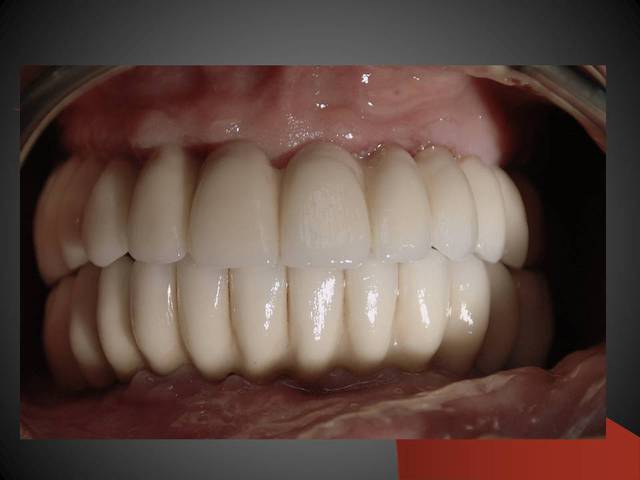

Un cas qui va sans doute prêter à discussions, juste pour montrer que la technique MIMI (non invasive) peut donner des résultats de qualité et esthétiques en moins de temps qu une chirurgie dite traditionnelle.

Les deux premières photos montrent le cas d´une jeune femme ( qui malheureusement s est fait retiré toutes les dents à l´étranger....).Ce cas a pu être terminé deux semaines après l´implantation.

Les deux dernières photos montrent le même cas deux ans plus tard.